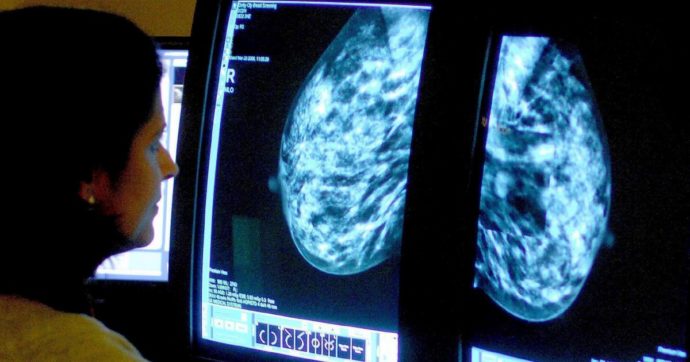

L’agenzia del farmaco Aifa assicura “l’intendimento di concludere l’iter negoziale del farmaco nel più breve tempo possibile”. Parliamo di Enhertu, il costoso anticorpo monoclonale coniugato che allunga la vita delle donne colpite da alcuni dei più gravi tumori della mammella. Da luglio è a carico del Servizio sanitario nazionale per il carcinoma detto Her-2 positivo […]